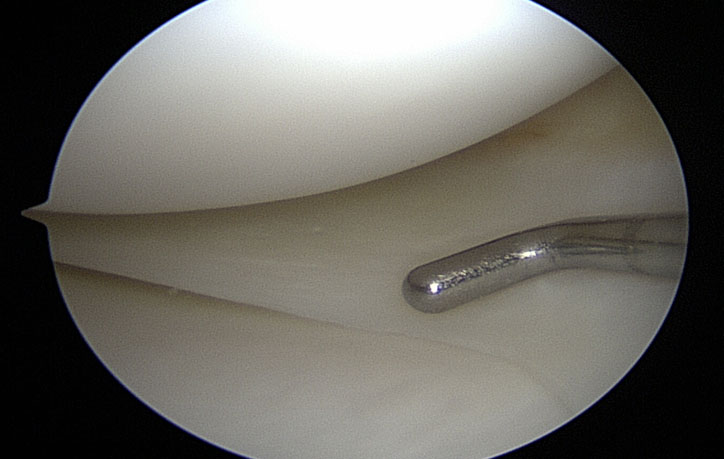

Reparación y remodelación de lesiones meniscales

Un menisco sano actúa como un amortiguador y un estabilizador a la vez que provee una superficie lisa para que la rodilla pueda deslizarse libremente. Una lesión meniscal altera este desplazamiento causando dolor y bloqueo, por lo que es fundamental realizar su reparación.